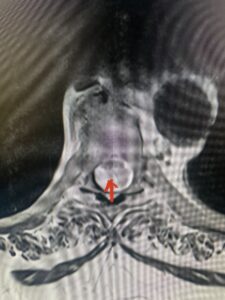

This 36-year-old female who had a long history of neck pain had a history on MRI of a C5-6 bulge. She recently after diving into a pool (not hitting her head on bottom) developed progressive problems with her arms. She had developed spontaneous shocks going down her arms and in the back of her neck. Spontaneous shocks going down the neck and spine is called a Lhermitte’s phenomenon and can occur with spinal cord compression and also with multiple sclerosis. On examination, the patient had long tract weakness of her arms, right greater than left. Her finger extensor weakness was profound on the right. MRI (Fig. 4) of the cervical spine revealed a massive C5-6-disc herniation causing significant cord compression right greater than left with subtle cord signal change. Because of the severe myelopathy, the patient was indicated for surgery. A C5-6 anterior cervical discectomy and fusion was performed (Fig. 5). The patient had a dramatic improvement of her strength in the recovery room.

Fig 4. Axial T2-weighted MRIs demonstrating large C5-6 herniated disc with spinal cord compression (red arrow)

Fig 4A. Axial T2 weighted MRIs demonstrating large C5-6 herniated disc with spinal cord compression (red-arrow)